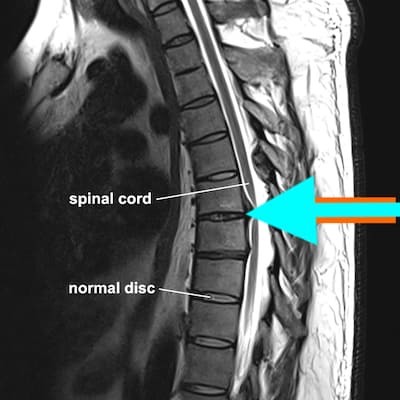

Магнитный резонанс позвоночника груди является одним из самых информативных методов диагностики. Этот метод позволяет обнаружить самые маленькие патологические изменения вокруг: повреждение позвоночника, инфекционного фокуса, опухолей, изменений в строительстве и установлении кругов и ряда других явлений без повреждений здоровья пациента.

Работа устройства основана на принципе магнитного ядерного резонанса: производство сильного магнитного поля приводит к следующим реакциям атомных частиц — протонов. Эта реакция записывается устройством и преобразуется в графический формат. Начальный продукт представляет собой трехмерные ломтики исследованных анатомических структур.

Магнитная томография на груди позвоночна для обнаружения локальных патологий, таких как проблемы со структурой, местоположением и суставами межпозвонковых дисков, рака, инфекций и т. д. Частый симптом, что приводит к необходимости назначать диагноз, это боль.